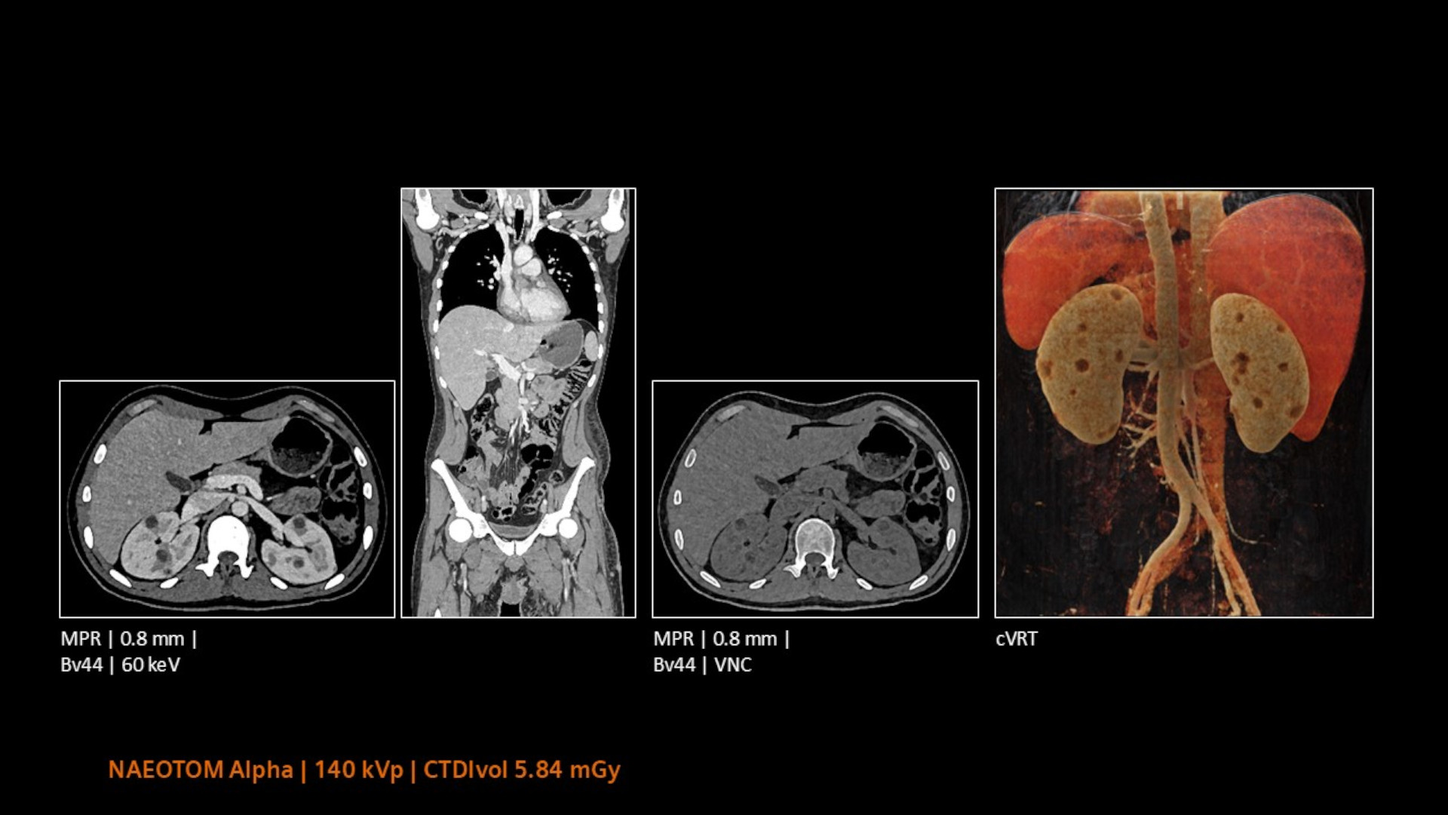

Che si tratti di imaging ad alta risoluzione, di imaging ad alto contrasto e a basso dosaggio o di imaging spettrale, Quantum Technology consente una stadiazione e un monitoraggio coerenti e precisi senza alcun compromesso. Tutti i risultati della TC rilevanti possono essere ottenuti con una sola scansione.

Il processo decisionale clinico può essere portato a un livello completamente nuovo grazie alla visualizzazione di caratteristiche oncologiche come tumori e vasi sanguigni che nutrono il tumore.